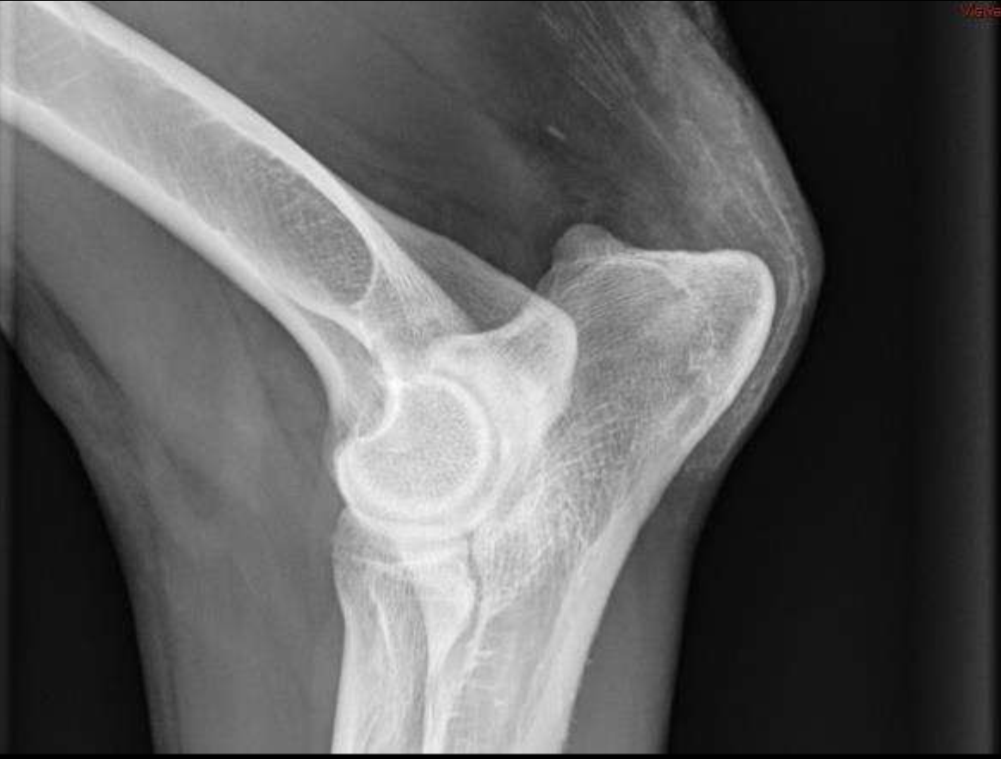

Which is more aggressive?

Right